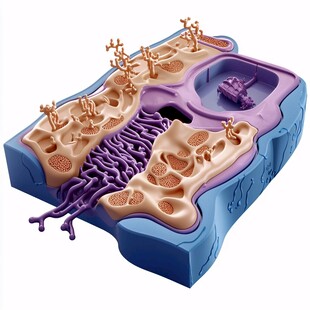

人体器官 商用作品

人体器官 商用作品 -

人体器官 商用作品

人体器官 商用作品 -

人体器官 商用作品

人体器官 商用作品 -